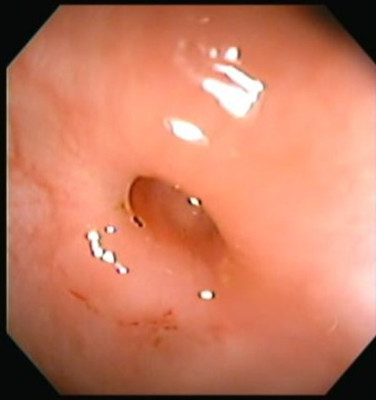

Enfermedad diverticular del colon

Envíado por Dr. Carlos Ernesto Arévalo